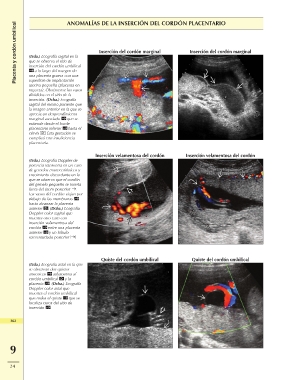

Placenta y cordón umbilical ANOMALÍAS DE LA INSERCIÓN DEL CORDÓN PLACENTARIO

(Izda.) Ecografía sagital en la Inserción del cordón marginal Inserción del cordón marginal

que se observa el sitio de Inserción velamentosa del cordón Inserción velamentosa del cordón

inserción del cordón umbilical

Quiste del cordón umbilical

a lo largo del margen de

una placenta gruesa con una

superficie de implantación

uterina pequeña (placenta en

raqueta). Obsérvense los vasos

divididos en el sitio de la

inserción. (Dcha.) Ecografía

sagital del mismo paciente que

la imagen anterior en la que se

aprecia un desprendimiento

marginal asociado que se

extiende desde el borde

placentario inferior hasta el

cérvix . Esta gestación se

complicó con insuficiencia

placentaria.

(Izda.) Ecografía Doppler de

potencia transversa en un caso

de gemelos monocoriónicos y

crecimiento discordante en la

que se observa que el cordón

del gemelo pequeño se inserta

fuera del útero posterior .

Los vasos del cordón viajan por

debajo de las membranas

hasta alcanzar la placenta

anterior . (Dcha.) Ecografía

Doppler color sagital que

muestra otro caso con

inserción velamentosa del

cordón entre una placenta

anterior y un lóbulo

succenturiado posterior .

(Izda.) Ecografía axial en la que Quiste del cordón umbilical

se observan dos quistes

anecoicos adyacentes al

cordón umbilical y la

placenta . (Dcha.) Ecografía

Doppler color axial que

muestra el cordón umbilical

que rodea el quiste que se

localiza cerca del sitio de

inserción .